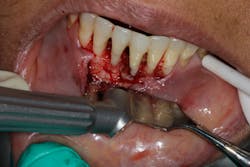

- Proper surgical technique including incision, flap design, and complete detoxification of bony defect and root apices (figures 3 and 3a)